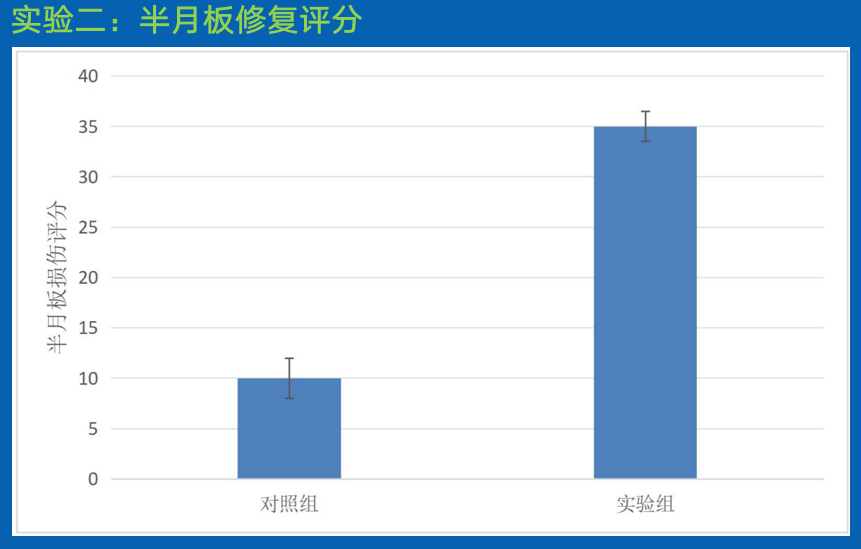

结论:

相比于对照组而言,实验组处理下的半月板修复显著提高,且差异极其显著。

由此证明,本发明实施例得到的组合物可用于修复半月板损伤。